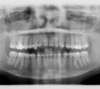

Les radios avant le traitement